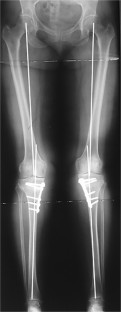

Fig. 2